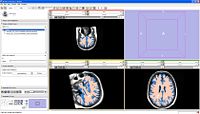

In this screenshot CompareView layout of 3D Slicer is used to facilitate visualization of multiparametric MRI of the prostate